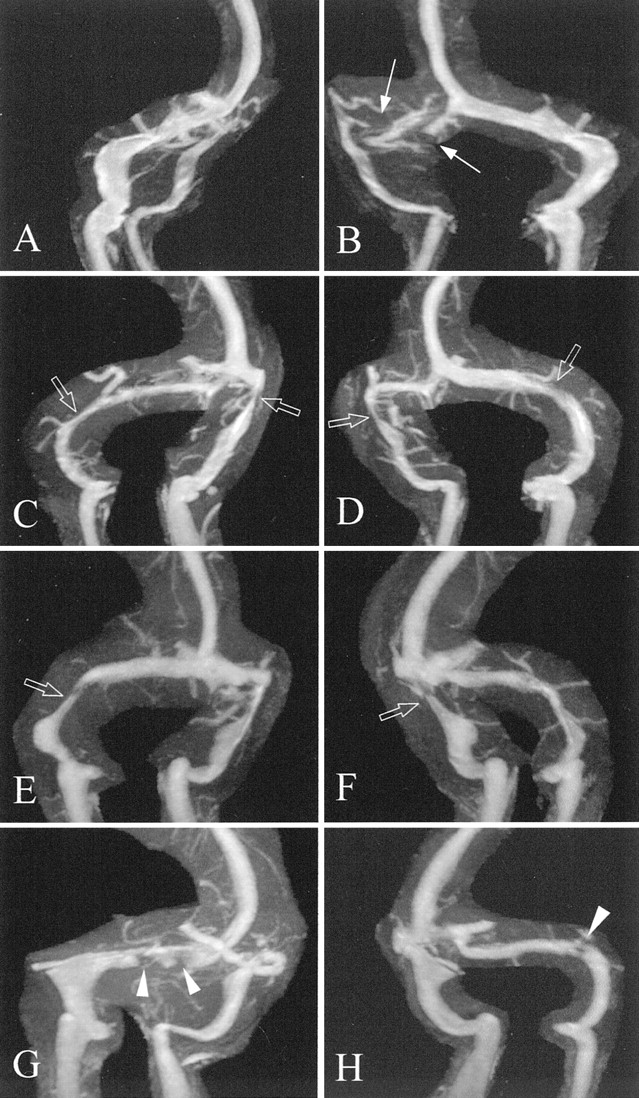

图1所示。Auto-triggered elliptic-centric-ordered控制病人的三维先生gadolinium-enhanced造影术。(一)横向和(B)前后的最大强度投影(MIPs)显示轮廓用来创建序列的分段MIPs获得每个控制和颅内高压症病人。(汉英)前后的左前斜(老挝),右前斜(RAO)分段MIPs。这三个选择拍摄的图像90张图片,电影圈的读者了。

图3。Auto-triggered elliptic-centric-ordered三维gadolinium-enhanced先生造影术发现颅内高压症患者。老挝和饶分段最大强度投影(A和B)病人77;(C和D)病人36;和(E和F)病人8。(A)不连续(得分= 0)被认为在右侧横窦(箭头)(B)。extralumenal压狭窄的例子(打开箭头)在(B-F)。经管障碍物的例子被认为双边(箭头)病人69 (G和H)。